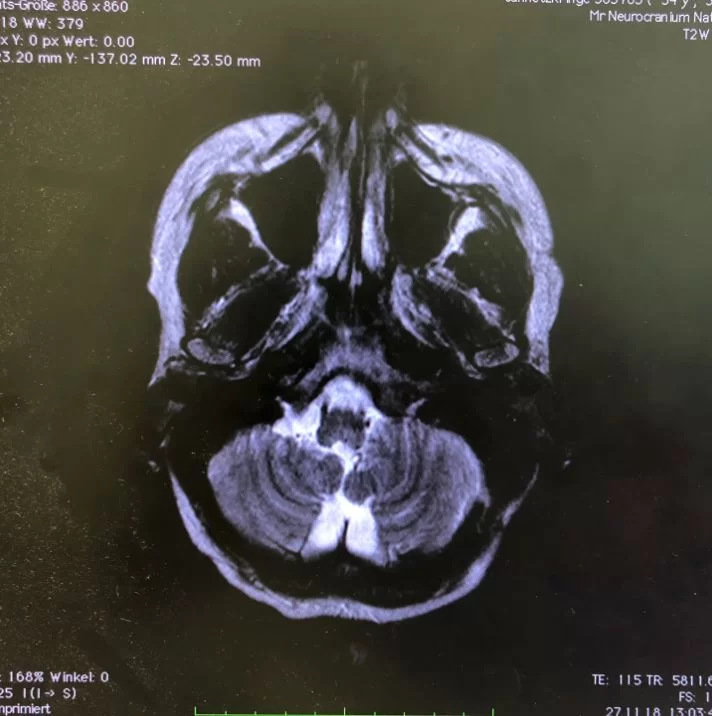

Ο προεγχειρητικός έλεγχος ανέδειξε μηνιγγίωμα της κρανιοαυχενικής συμβολής με εγκολεασμό σημαντικών αγγειακών και νευρικών δομών και επέκταση προς την αντίθετη πλευρά.

Πρόκειται για ένα εξαιρετικά απαιτητικό χειρουργείο λόγω της θέσης του όγκου. Παρόλο που πρόκειται για μια καλοήθη βλάβη (μηνιγγίωμα), ο όγκος αναπτύσσεται στο ύψος του ινιακού τρήματος και εγκολεάζει πολύ σημαντικές νευραγγειακές δομές. Επιπλέον, η μορφολογία του όγκου είναι εξαιρετικά σύνθετη, μια και επεκτείνεται έμπροσθεν του στελέχους του εγκεφάλου στην απέναντι (δεξιά) μεριά.